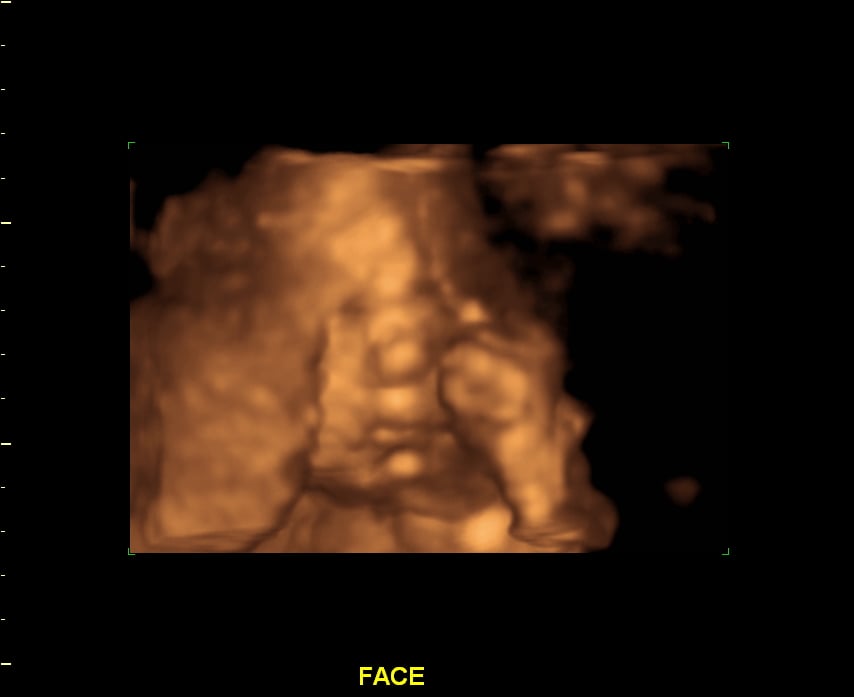

Patiently waiting for little brother!